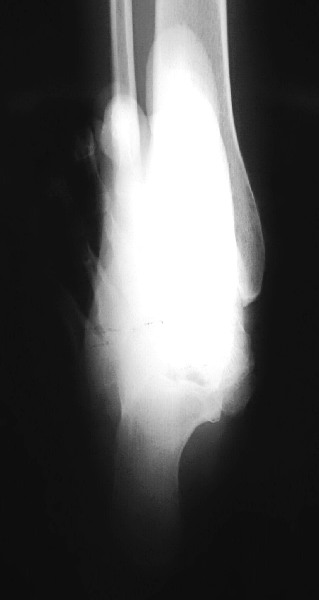

Pertinent Points On Diagnostic Imaging

Assess standard weightbearing views (AP, lateral and oblique views of the foot and ankle) for degenerative changes and angular deformity. Evaluating ankle films helps in ruling out a valgus deformity within the ankle joint. One can measure the talo-first metatarsal angle on AP and lateral foot radiographs. Obtaining a hindfoot alignment view and long leg calcaneal axial views can help in determining the level of valgus deformity (STJ vs. AJ vs. calcaneus). When assessing adolescent patients, clinicians should rule out tarsal coalitions. Obtaining a MRI can be helpful to rule out fibrous or cartilaginous coalitions in these patients. Advanced imaging is also beneficial to evaluate joint integrity when deciding between joint sparing procedures or an arthrodesis.